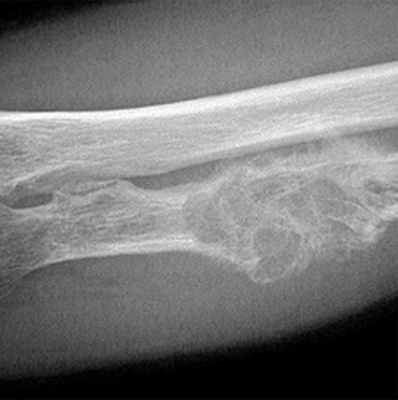

• Рентгенография обычно позволяет выявить литическое образование. Некоторые опухоли молочной и предстательной желёз на рентгенограммах представлены бластическими образованиями •• Остеолиз визуализируется рентгенологически при разрушении 40–50% костной ткани и достижении размеров более 1 см, сопровождается гиперкальциемией и экскрецией содержащих гидроксипролин пептидов •• Остеобластические повреждения выявляют при радионуклидном сканировании костей и рентгенологическом исследовании (увеличение плотности кости и склероз). Остеобластические повреждения могут сочетаться с увеличением в сыворотке крови концентрации ЩФ и гипокальциемией.

- Деструкция с «разъеданием» костной структуры на рентгенограммах выглядит как дефект – «дырка», такой вариант метастазирования называют остеолитическим, что буквально означает «съеденная кость».

- При утолщении кости за счёт опухоли рентгенограмма выявляет «плюс ткань», тогда говорят об остеопластическом метастазировании.

- Как правило, у больного встречаются оба вида метастазов с превалированием одного из вариантов, в большинстве случаев остеолитического.